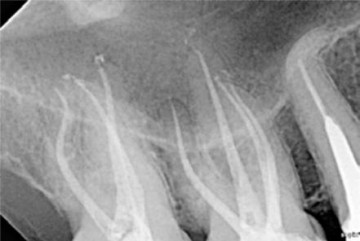

Postoperative x-ray. Both molars were shaped using the 2Shape sequence. The apical finishing of the palatine canals was carried out with a F35 file.